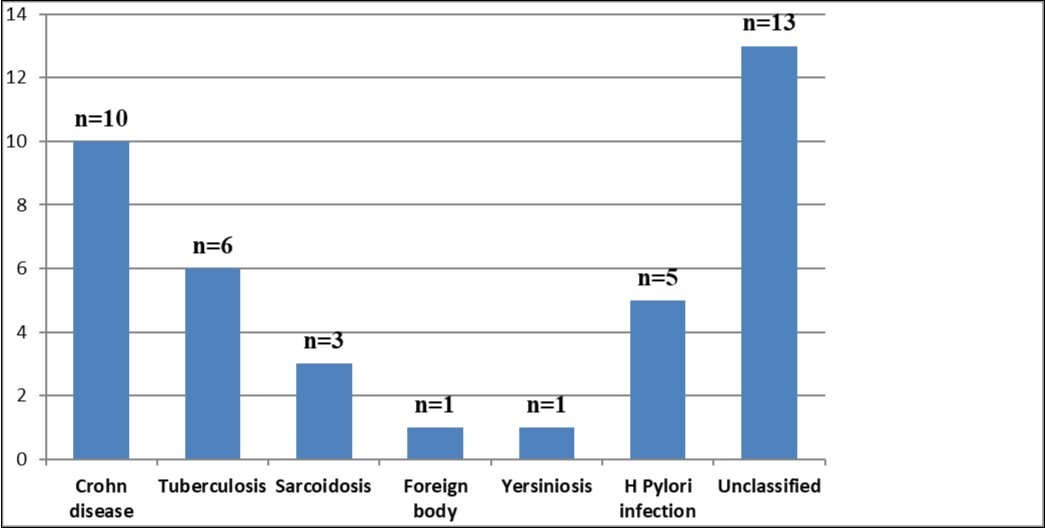

Biopsies from the 39 patients diagnosed as having granulomatous gastritis were reviewed. Mean age was 49 years (24 – 96) and sex ratio was 0,25 (M/F=8/31). Indication of endoscopy was gastric pain in 12 cases, chronic diarrhea in 6 cases, anemia in 2 cases, vomiting in 4 cases. Other symptoms were rare. Upper endoscopy was normal in 8 cases, showed antral gastropathy in 20 cases (erythematous in 6 cases, nodular in 8 cases and ulcerated in 6 cases). In four cases, fundic lesions were observed. Granuloma was unique in 14 cases and multiple in 25 cases. Localisation of granuloma was the antrum in 25 cases, the fundus in 7 cases, and both of them in 7 cases. An associated chronic gastritis was noted in 25 cases. Concerning the etiology, 10 of our patients had Crohn's disease while 6 of them had gastric tuberculosis. In five cases, H Pylori was the retained cause of gastric granulomatosis. In the other patients, the final diagnosis was sarcoidosis (n=3), foreign body reaction (n=1), yersiniosis (n=1). In our series, thirteen cases were unclassifiable.

Concerning the etiology, diagnosis was made regarding to the past medical facts, the clinical symptoms, the endoscopic findings and the histological associated lesions. The main etiology was represented by Crohn’s disease in ten cases, followed by gastric tuberculosis in 6 cases. H Pylori was the retained cause of gastric granulomatosis in 5 cases, regarding to the absence of other etiologies, and the favorable issue after antibiotic eradication treatment. In 5 other patients, etiology of gastric granulomatosis was also found and the final diagnosis was a sarcoidosis (n=3), foreign body reaction (n=1), and yersiniosis (n=1). In our series, thirteen cases were unclassifiable despite etiological investigations and no cause of gastric granulomatosis was isolated. Histological findings of a case of tuberculosis and sarcoidosis are represented in Figure 1 and Figure 2.

In our cohort, no malignant or vascular disease as cause of GG was objectified. Causes of gastric granulomatosis are resumed in Figure 3.